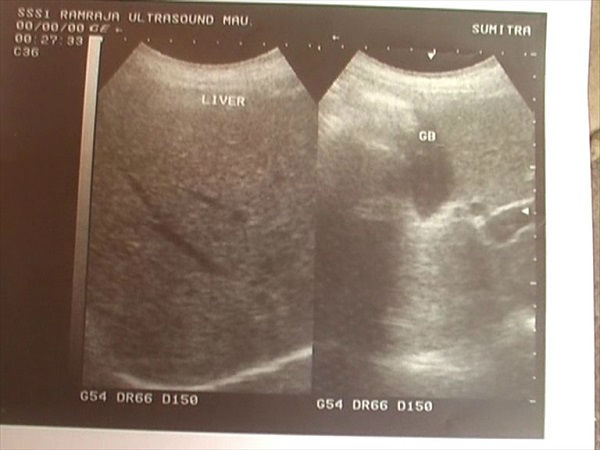

ये है अल्ट्रासाउंड की रिपोर्ट

तब दोनों किडनियां थीं

डॉक्टर के मुताबिक महिला का ऑपरेशन 7 अक्टूबर 2009 को हुआ था। उस समय कराए गए अल्ट्रासाउंड में उसकी दोनों किडनियां थीं। बीते माह जब महिला की तबीयत ज्यादा खराब होने लगी तो सुमित्रा का अल्ट्रासाउंड कराया गया। फिर डॉक्टर ने बताया कि सुमित्रा की तबीयत इसिलए लगातार खराब रहती थी क्योंकि उसकी एक किडनी निकाल ली गई थी।